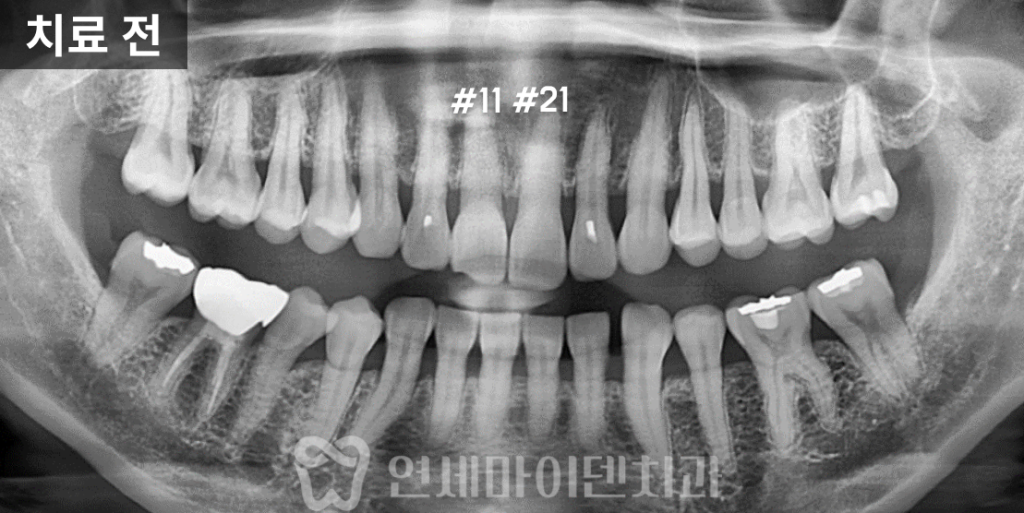

저희 병원에서 방사선 촬영을 진행한 결과,

실제로 신경관이 석회화된 모습이 확인되었습니다.

정상적인 치아처럼 신경관이 중앙에 선명히 보여야 하지만,

해당 앞니 두 개는 뿌옇게 흐려져 거의 보이지 않았습니다.

하지만, 신경관이 보이지 않는다고

신경관이 존재하지 않는 것은 아닙니다.

석회화로 인해 찾기 어려울 뿐,

내부에는 여전히 신경관이 존재합니다.

즉, 신경관을 찾을 수만 있다면 신경치료는 가능합니다.